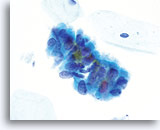

Biopsie

Papillär-seröses Endometriumkarzinom

Gleiche Patientin, gesplittetes Zellmaterial

Biopsie

Papillär-seröses Endometriumkarzinom

Gleiche Patientin, gesplittetes Zellmaterial